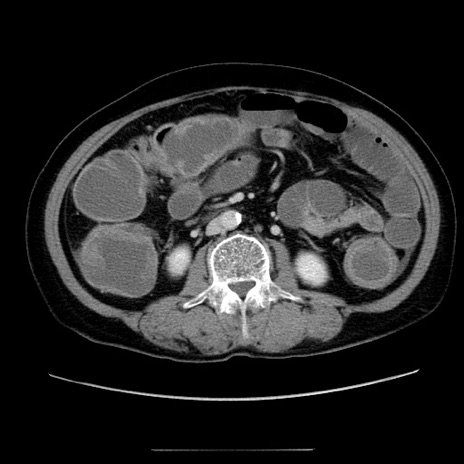

症例5(横断像)

【症例】70歳代女性

【主訴】お腹が張る

【現病歴】1週間くらい前から腹部膨満の自覚あり。昨日夜から増悪したため、本日救急外来受診。

【身体所見】意識清明、BT 36.5℃、BP 165/106mmHg、HR 80bpm、SpO2 98%、腹部:膨満、軟、自発痛・圧痛なし、触診にて不快感あり、腸蠕動音:減弱

【データ】WBC 12600、CRP 1.04